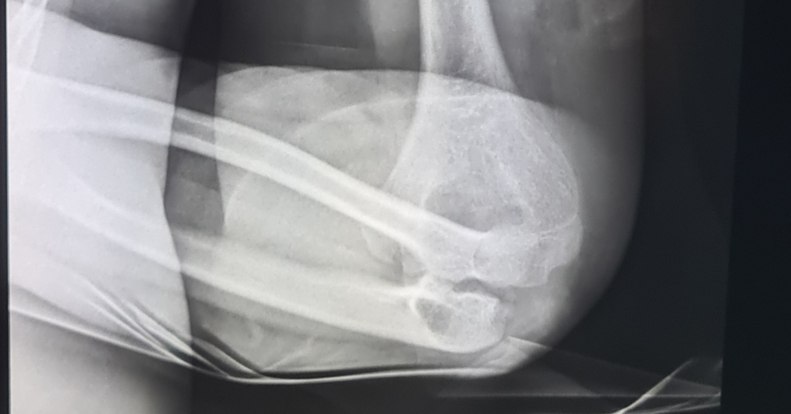

Bandi története megrázó, de korántsem egyedi. A 13 éves fiú szüleitől kapta első elektromos rollerét jó tanulmányi eredményeiért. Az öröm azonban nem tartott sokáig: másnap egy kátyú miatt bukott, feje többször az aszfalthoz csapódott, karja pedig nyílt törést szenvedett. A sisakja behorpadt, de megmentette a koponyáját – nélküle a sérülés sokkal súlyosabb lehetett volna.

A Bethesda orvosai szerint ilyen és ehhez hasonló esetek szinte minden nap előfordulnak. A baleset utáni műtői beavatkozás, a gipsz, a rehabilitáció mind hosszú hetekre kiveszik a gyereket a mindennapokból, és mély nyomot hagynak a családban is.